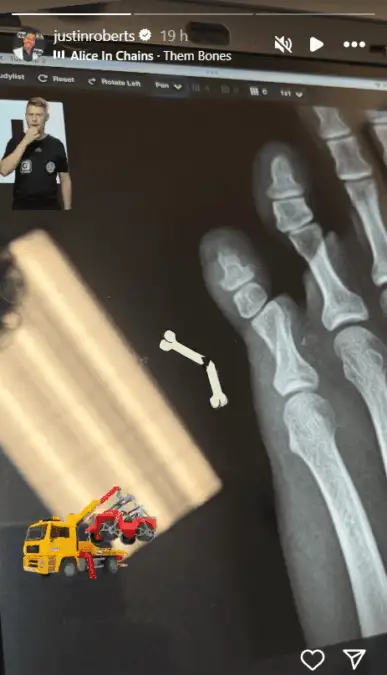

A revelação foi feita pelo próprio Roberts em sua conta no Instagram. Ele publicou uma imagem do raio-X, que mostrava claramente a fratura, acompanhada por um emoji de osso quebrado e a música “Them Bones”, da banda Alice in Chains.